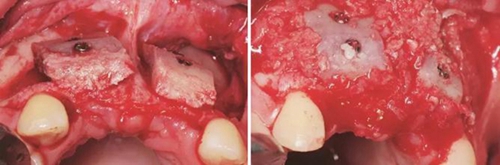

圖7 受植區(qū)固定髂骨骨塊 圖8 自體骨屑與人工骨粉混合后充填植骨間隙

圖9 嚴(yán)密縫合創(chuàng)口 圖10 植骨后拆線

圖11 植骨后6月種植術(shù)前 圖12 種植術(shù)前翻瓣后見少量鈦釘螺紋暴露